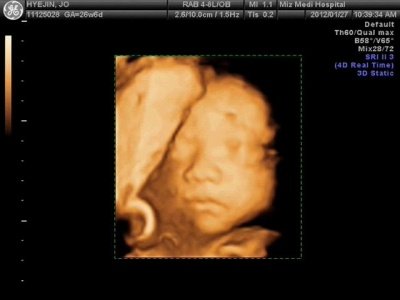

우리 튼튼이 3D 초음파 영상입니다.

이모야도 사진 보는 순간 너무 감동해서 울컥통곡했더랬죠. ㅎ